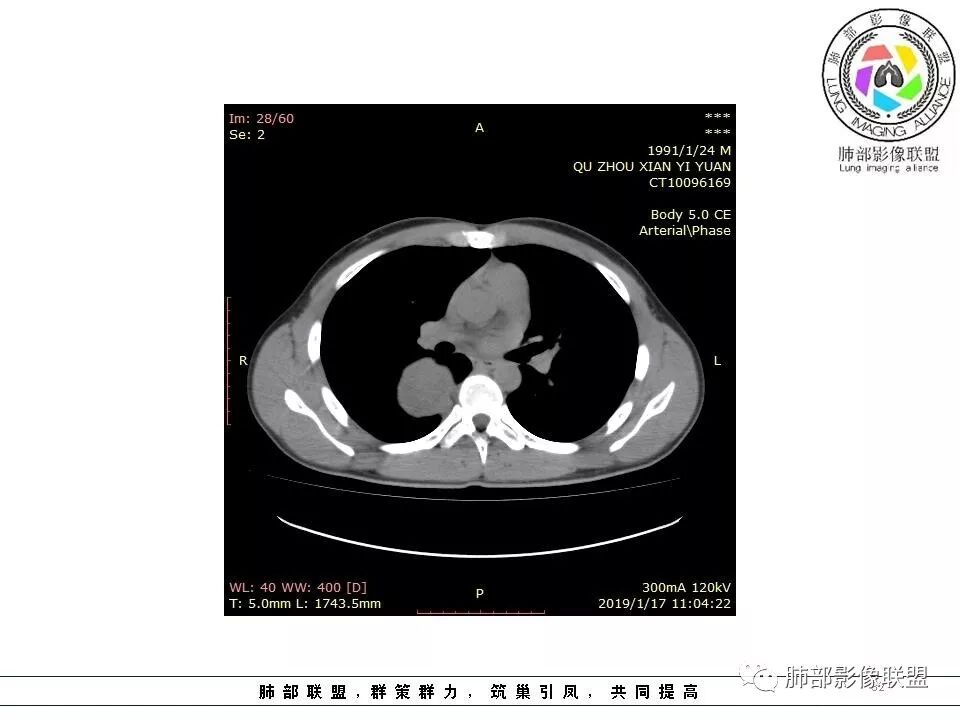

右后纵膈脊柱旁软组织占位,形态规则类圆,边缘光整,肺组织受压,胸膜尾,肋间动脉供血。中度不均匀延迟强化。

后纵隔脊柱旁占位性病变,疾病谱有神经鞘瘤,sft,节细胞瘤,髓外造血。此例有胸膜尾征,蛇纹征 ,延迟强化。考虑胸膜孤立性纤维瘤。看到有供血动脉,但不知道是哪里的血管。

病灶定位脏层胸膜,肺组织受挤压,有胸膜尾征,动脉期可见血管支配,考虑肺动脉供血,静脉期,强化增强明显,符合快进慢出特点,病灶内可见低密度区,考虑胸膜孤立纤维瘤。

青年男性,右侧脊柱旁软组织肿块,边缘膨隆,密度不均,临近肺组织受压、胸膜增厚,增强后动脉期呈不均匀强化,并可见肋间动脉供血,延迟期强化较均匀,定位肺外,首先考虑SFT,神经源性肿瘤待排

青年男性,胸痛,右上纵膈脊柱旁肿块,形态光整规则,支气管被推移,临近的胸膜明显增厚,有胸膜掀起,增强后密度不均匀,可见蛇形血管征,血供似乎有两根血管供血,考虑SFT

右上肺野脊柱旁软组织肿块,边缘光滑整齐,肺组织及气管右肺上叶支气管受压前移,外移,边缘可见胸膜尾征,病灶内密度不均,增强后渐进性持续强化,其内可见明显蛇纹血管征,首先考虑肺外来源,sft.可能性大

青年男性,右侧脊柱旁占位,瘤肺界限清晰,支气管推移,胸膜尾,D字征,胸膜下脂肪影,蛇纹血管,双重供血,延迟强化,定位胸膜,支持sft

边缘光滑,宽基底与胸壁相连,跨叶裂,叶裂稍前推,血管、支气管前移。

浅分叶

外上侧少量胸水

肋间动脉供血,强化尚均匀,逐步强化